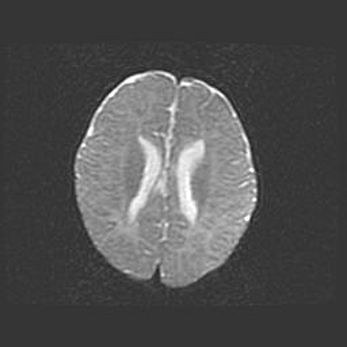

Неполная лизэнцефалия (пахигирия). Открытая гидроцефалия.

Возраст: 17 дней

Вес: 3110 г

Пол: мужской

Окружность головы: 33,5 см

Срок гестации: 35-36 недель

Лизэнцефалия—недоразвитие корковой пластинки и мозговых извилин в результате нарушения миграции нейронов коры. Поверхность мозговых полушарий гладкая. Микроскопически выявляется отсутствие нормальных слоев коры и скопление групп нейронов в подкорковом белом веществе.

Пахигирия—уменьшение числа вторичных извилин. В пораженном полушарии нервные клетки образуют толстый недифференцированный слой с неправильно расположенными нервными волокнами и группами гетеротопных клеток. Нервные клетки незрелые. Белое вещество истончено. При этом нередко аномально развит корково-спинномозговой путь.